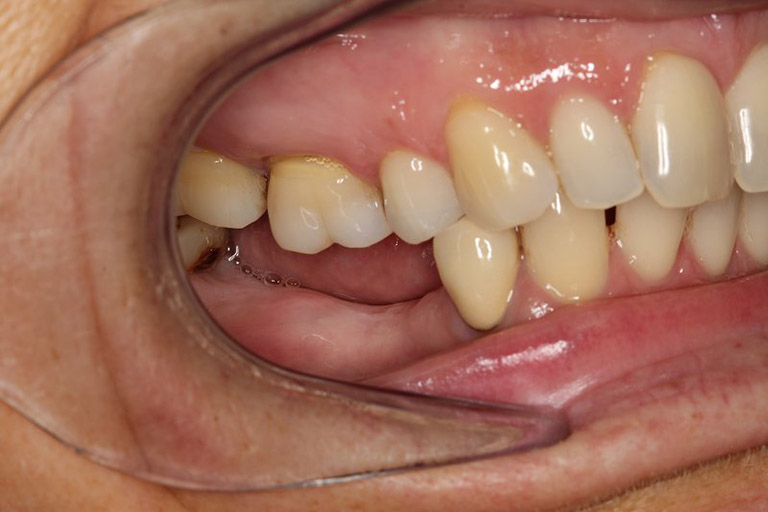

Cô Đinh Thị Anh Đào có cụm răng mất 5 răng liên tiếp cần trồng 3 trụ, làm 5 răng lên trên